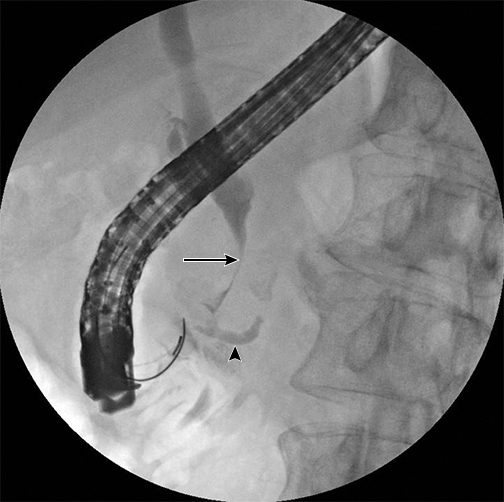

This 55 year old man with Peutz-Jeghers syndrome underwent an ERCP for nausea, vomiting, and abdominal pain. The arrow shows the common bile duct. The arrowhead shows the pancreatic duct.

Challenge: What's your diagnosis?